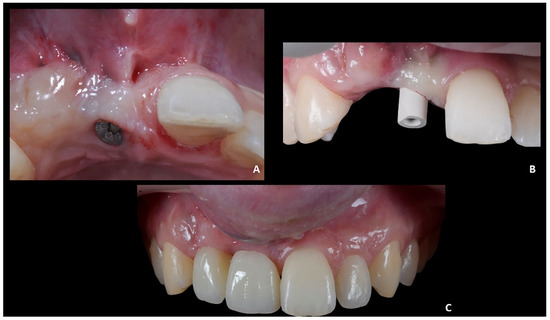

Figure 11. Case 2. (A) Healing abutment; (B) intra-oral scan with scan-body to detect the axial orientation of the implant; (C) prosthetic restoration.

The first part of the therapy consisted of removing the causes of inflammation in the anterior segment, respectively, in the edentulous area removing the fixing screw and around natural teeth by performing professional oral hygiene and scaling (Figure 8B). After that, the treatment plan for implant-prosthetic rehabilitation of the 2.1 was performed and supported by digital systems:

• Prosthetically guided implant planning. After removing the provisional prosthesis, an intra-oral scan was recorded, and the lab technician was asked to produce a virtual wax-up of the ideal position of the teeth. A Cone-Beam Computed Tomography (CBCT) was performed, and the 3D rendered model of the maxilla was registered with the intra-oral scan using the implant planning software Co-Diagnostix (Straumann, Montreal, Canada) (Figure 9). The software was used to plan the implant’s ideal position and design a surgery guide. Figure 10 shows the clinical procedure of the guided implant surgery. Once the osseointegration occurred, an intra-oral scan was performed to register the position of the implant and the surrounding soft tissues with the healing abutment in place (Figure 11A,B).

Positioning of the provisional prosthesis (11 with cantilever 1.2). The scan file was sent to the lab technician, which was asked to design a fixed temporary prosthesis in polymethyl methacrylate (PMMA), screwed onto the implant, and with the following instructions: (1) designing the 1.1 and 1.2 with the same size of contralateral teeth, and (2) maintaining the ideal overjet and overbite ratio compared to opposite arch (Figure 11C).